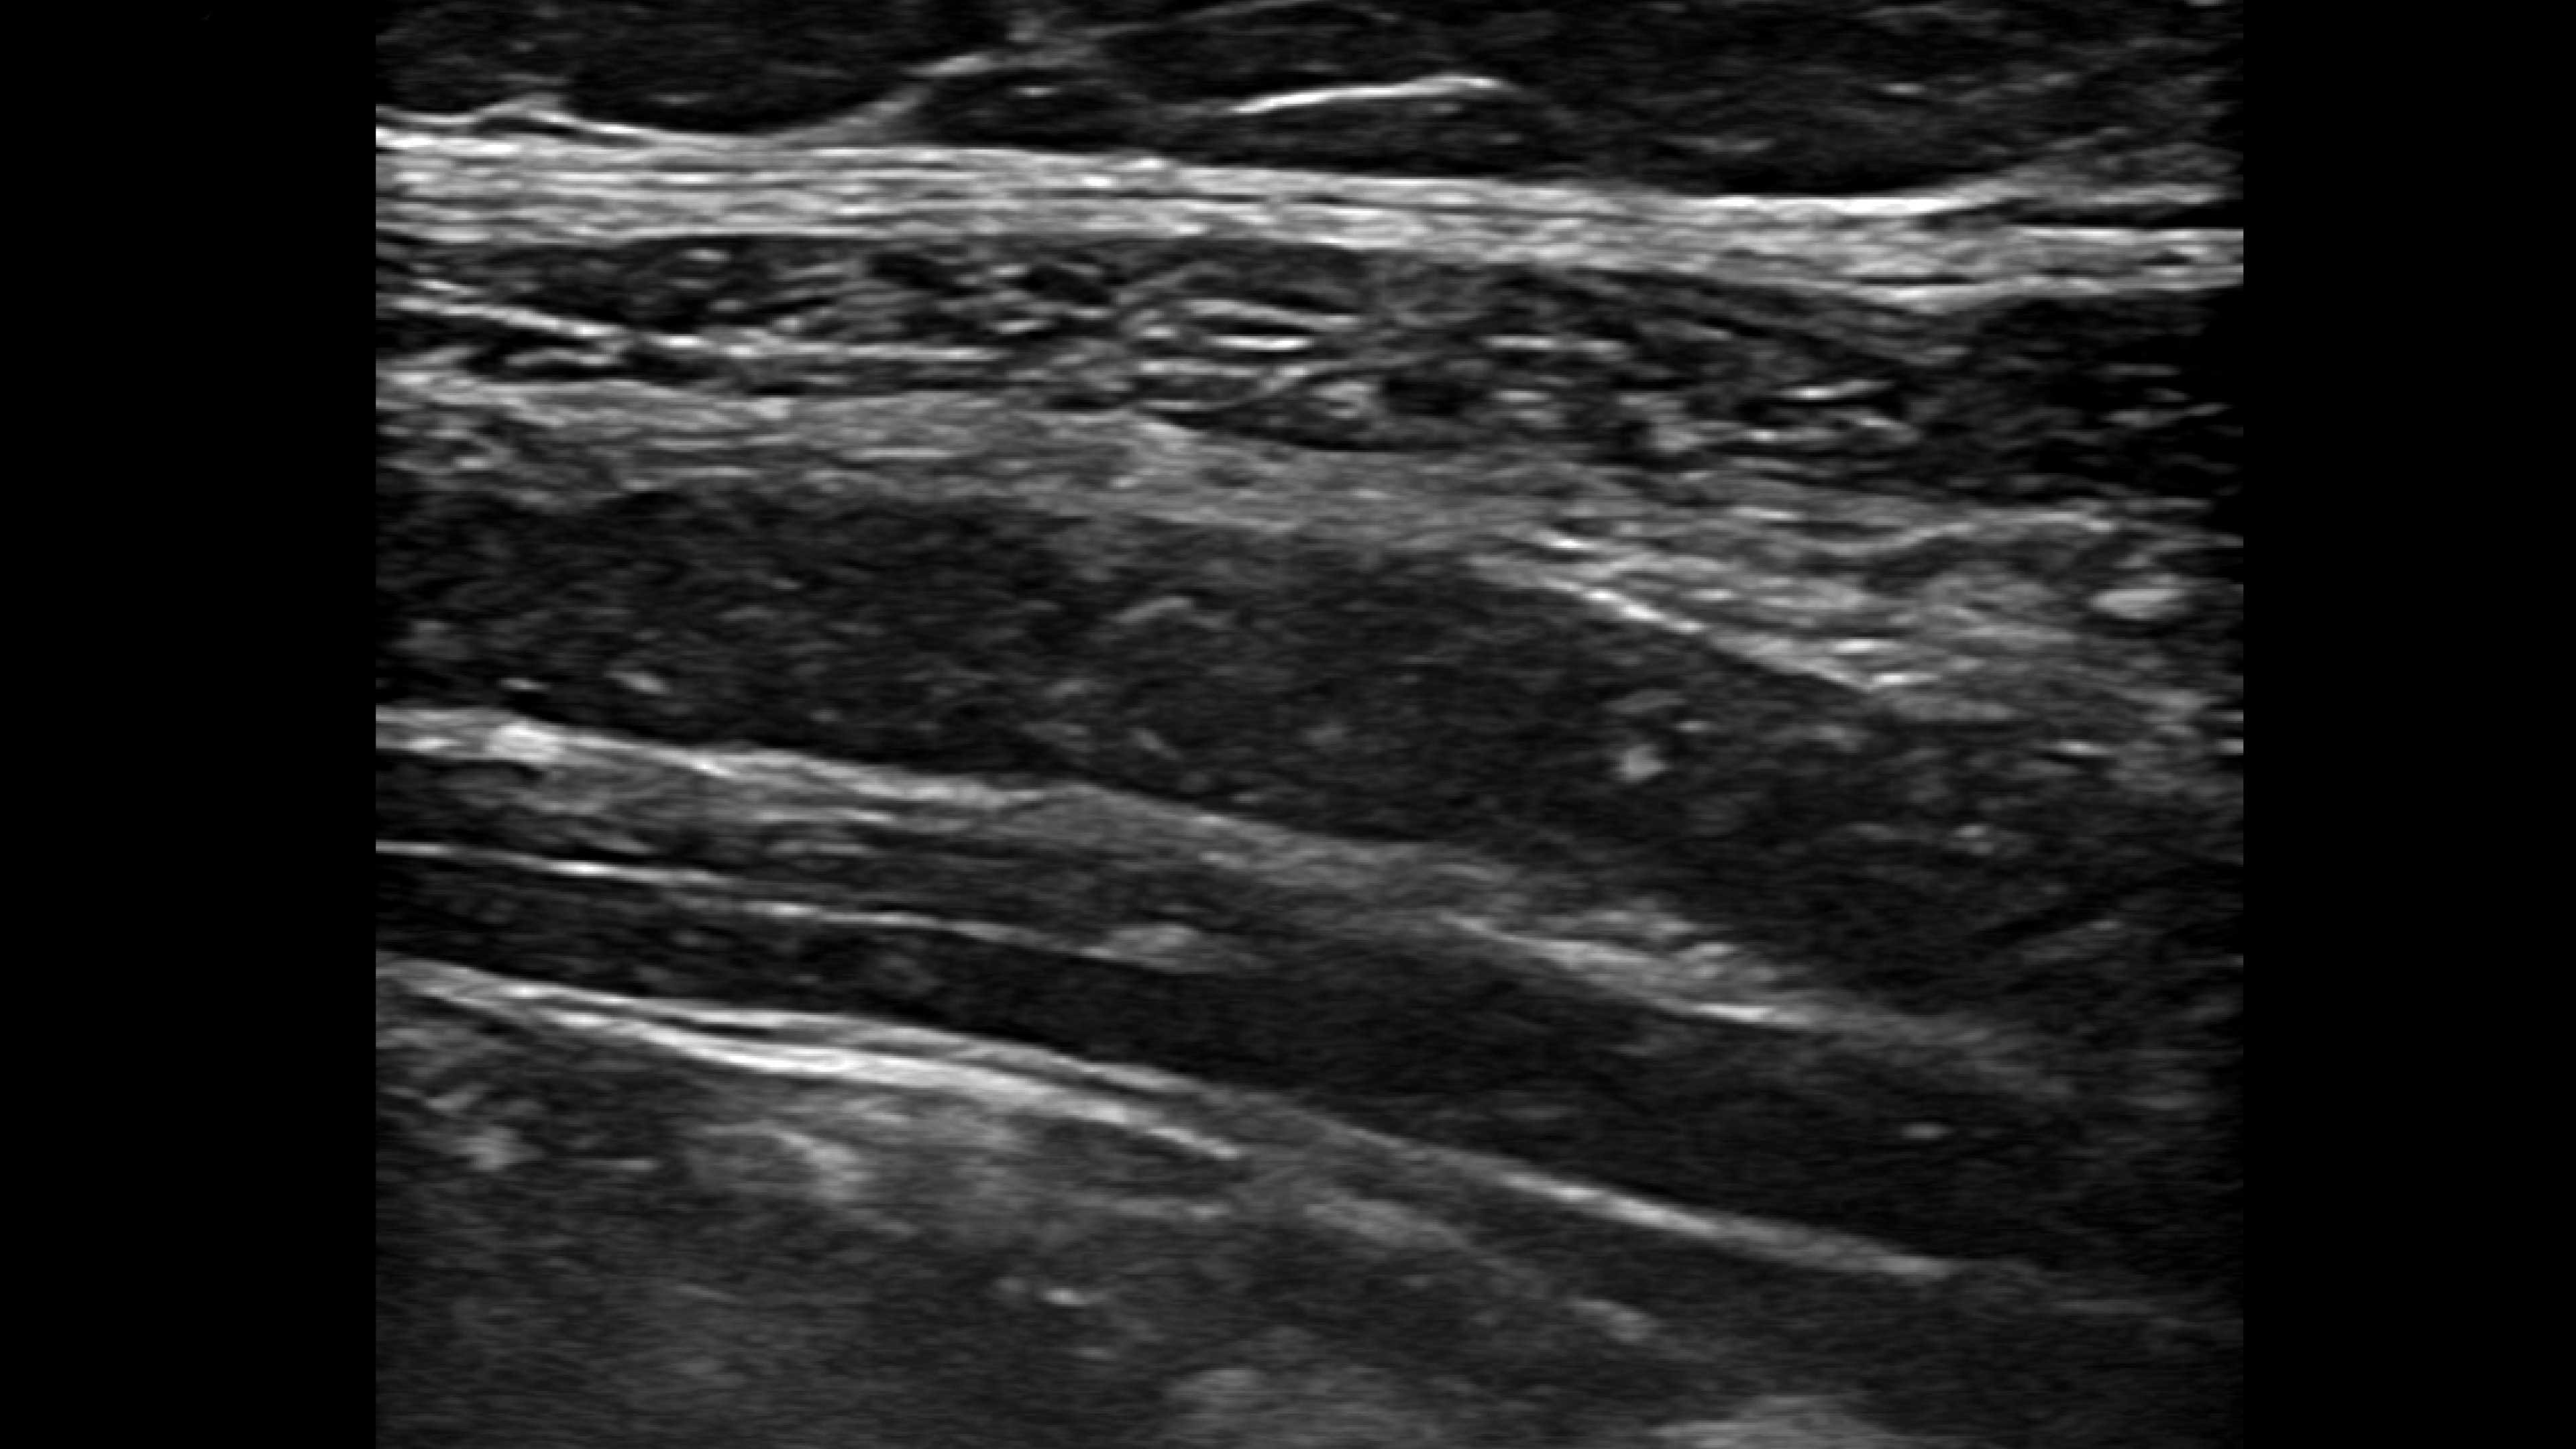

Small yet powerful

Flexible, wireless dual-probes deliver clear images and Venue family software